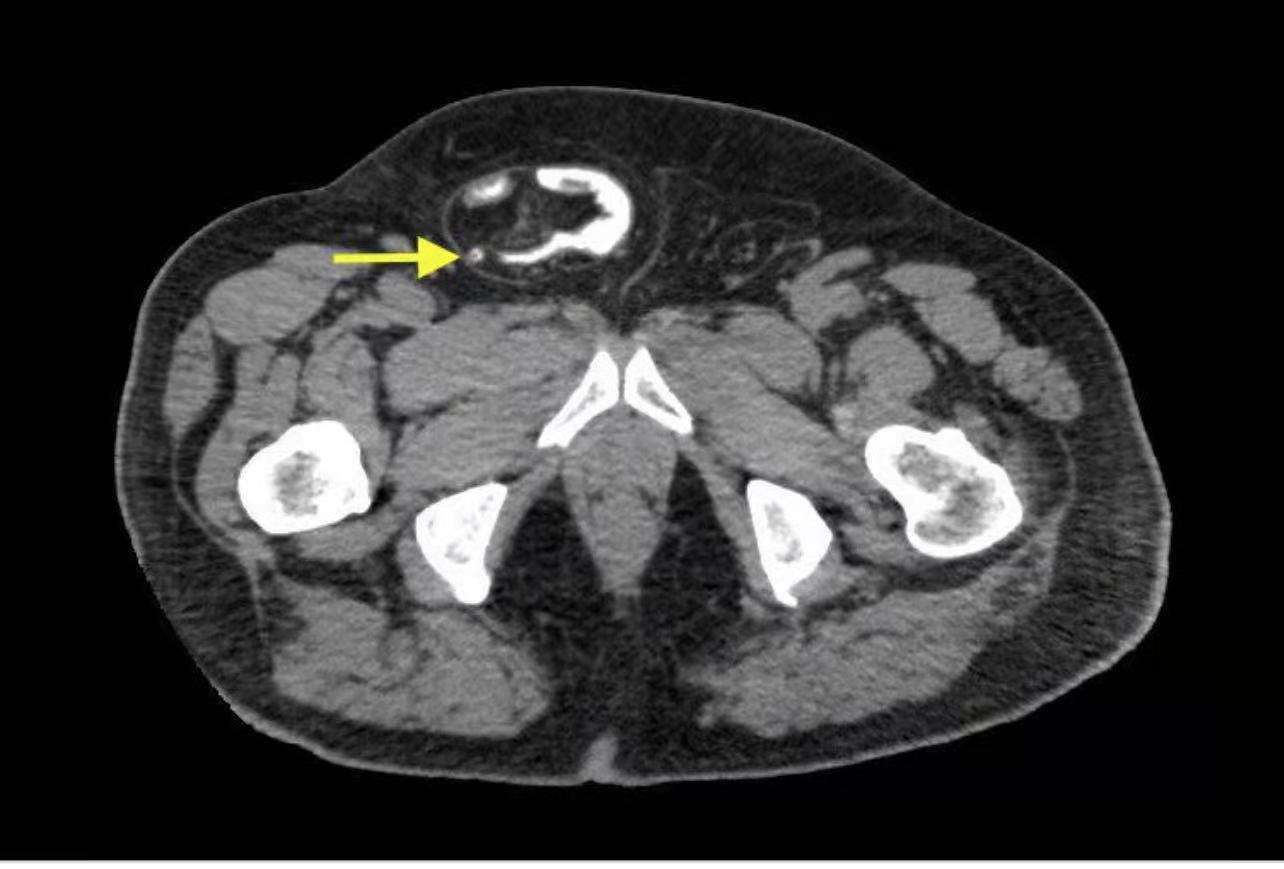

一個好的疝氣管理中心,就應該要有收治各式各樣的疝氣類型的本事,在全方位疝氣中心裡,總是會碰到一些奇奇怪怪罕見的病例。 做為一個專責的疝氣治療院所,千奇百怪的案例我們真的是看得多了,但中心的朱紀洪院長真的是百毒不侵,總是遇到疑難雜症款的疝氣,而這次的個案,罹患疝氣的名稱叫「Amyand Hernia」咦?你會以為疝氣不就是疝氣嗎?怎麼有那麼多花樣?!但不細說,還真的是個案數的大眾疝氣手術,會因體質、特殊病因性,而能見到一位外科醫師的真曉。 何謂Amyand Hernia? 其實這種疝氣才占了所有疝氣種類的1%都不到,而幾乎都是發生在男性。這樣解釋你可能還不是很清楚……如果說盲腸,可能大家就有點概念了,而Amyand Hernia 正式在疝氣囊裡面藏著盲腸,而我們全方位疝氣中心居然碰到了一位年輕男性罹患股溝疝氣併發盲腸炎,這個機率非常低,約0.07到0.13%而已,而我們中心的朱紀洪院長,靠著幾近完美的醫術和經驗,在手術前靠著小心診斷驗證,細心的評估檢查病人狀態,排除併發症的可能性,透過斷層掃描,再仔細判讀才發現他竟然碰到疝氣中的特案,且因為這讓手術的難度更是高升,還好透過朱院長精湛的手法和技巧,解決了病人的痛苦,也免除急性盲腸炎破裂,真是免除病人後續生命危險的可能性。